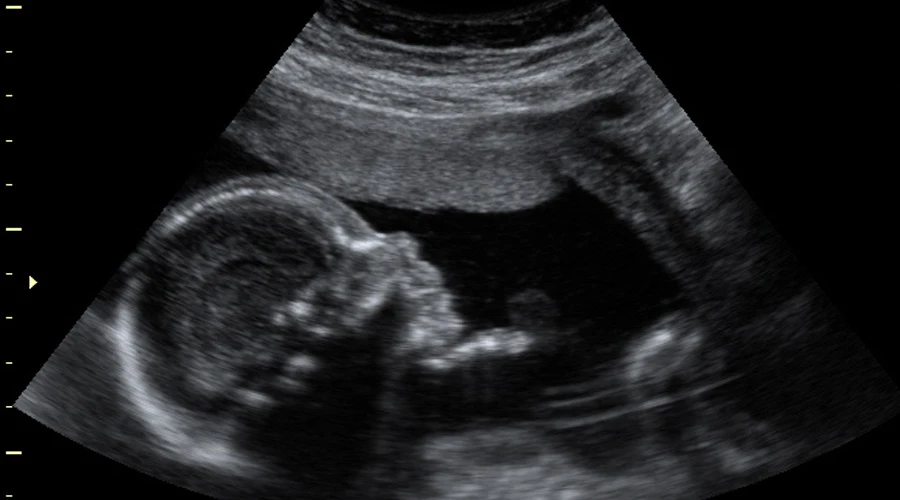

El término "hospice" perinatal hace referencia a la medicina fetal y a las curas paliativas prenatales, así como al acompañamiento del feto como paciente, incluso en las condiciones patológicas más extremadas.